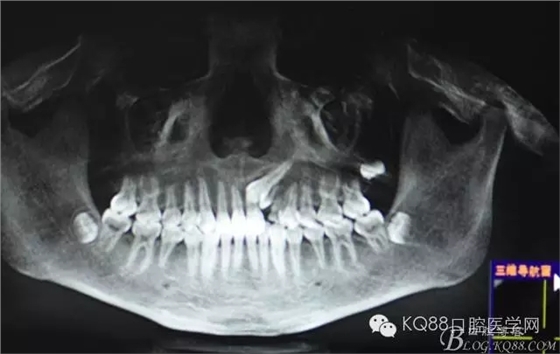

图2.全景片影像检查:23牙冠的远中还有一颗22畸形牙、及63滞留